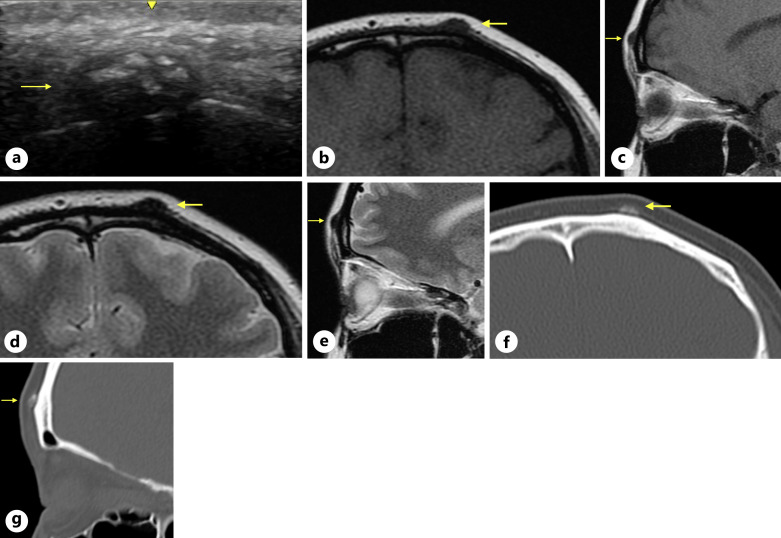

Case presentation: We present a case of primary osteoma cutis specifically located on the forehead in a young woman. Histopathological findings revealed a nodule of bone tissue within the dermis, along with some contiguous cartilage tissue. The patient underwent preoperative ultrasonography, computed tomography, and magnetic resonance imaging.

Conclusion: We report this case because there have been no reports of primary osteoma cutis with complete preoperative imaging findings to the best of our knowledge.